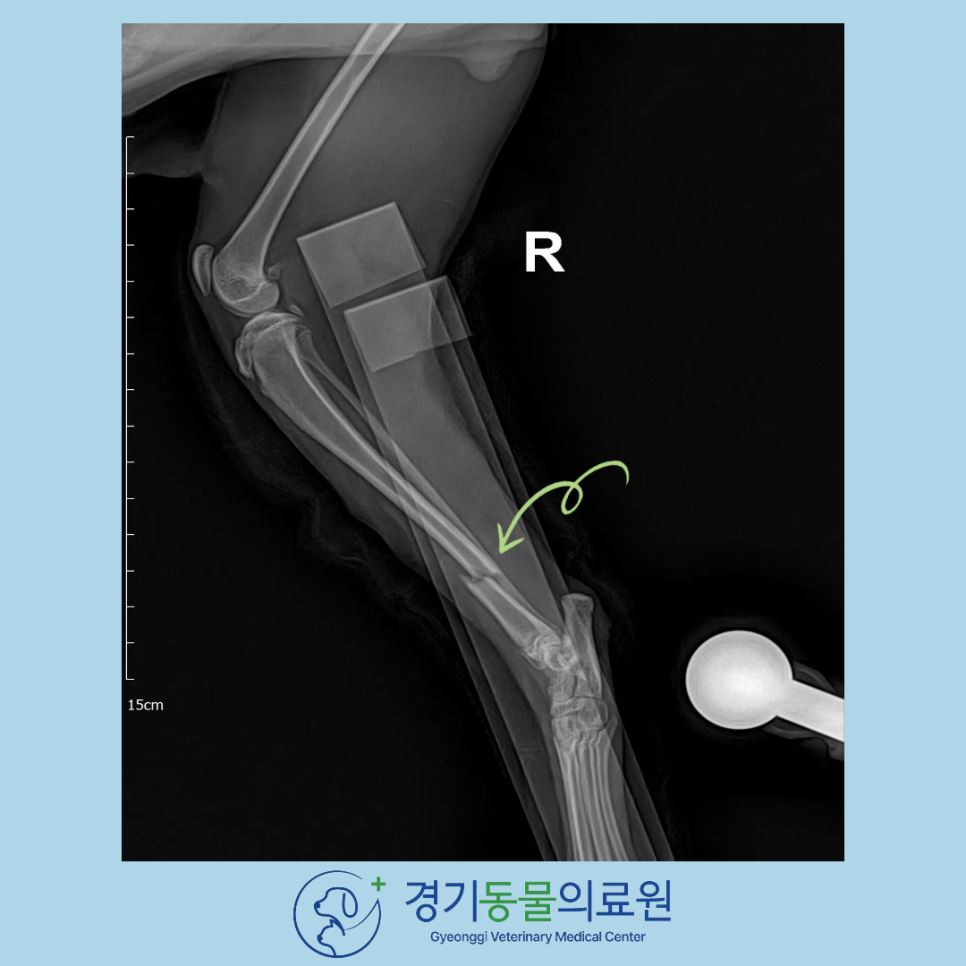

수술 전 X-ray 검사에서 정강이뼈(경골) 골절 확인

정확한 골절 평가를 위해 X-ray(엑스레이) 촬영을 시행하였습니다.

촬영 결과 경골 윈위부 골절이 확인되었습니다.

경골은 체중을 직접 지탱하는 뼈이기 때문에 보존적 치료 시 실패율이 높아 골절 수술이 필요한 경우가 대부분입니다.

<고양이 경골 골절 부위 방사선 평가>